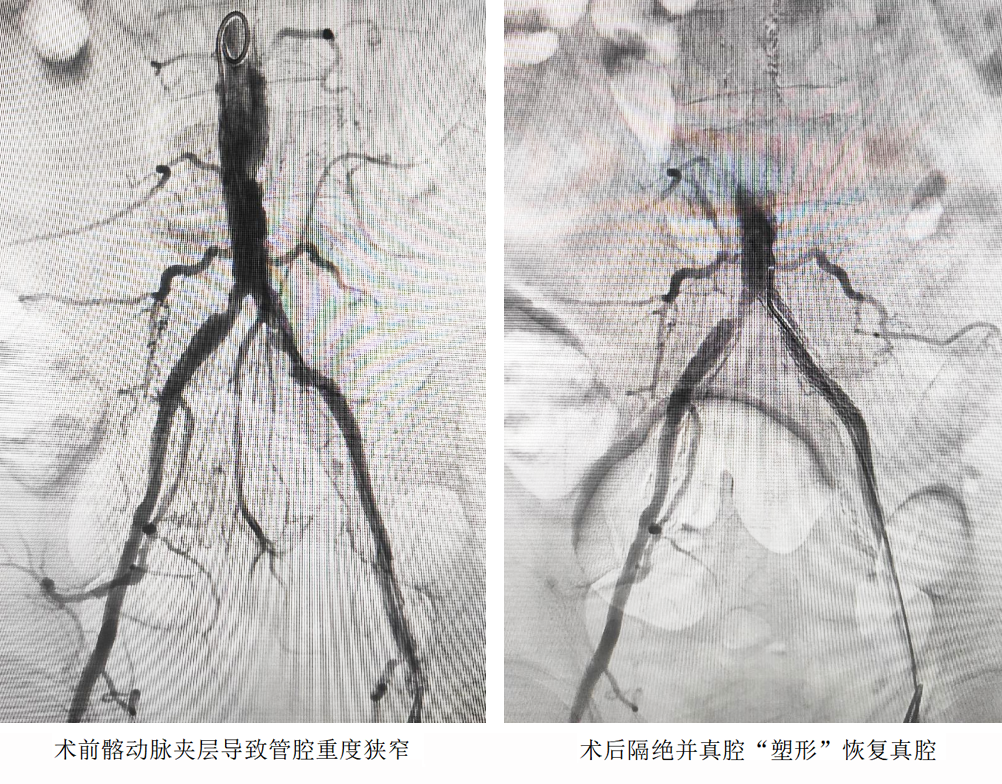

患者,男,66歲,因“左下肢重度間跛、皮膚蒼白、足背動脈搏動消失并夜間靜息痛”收入院。影像檢查顯示:左髂動脈夾層形成真腔狹窄,血流“斷崖式”下降;股總動脈被鈣化斑塊完全“封堵”;股淺動脈長段閉塞,閉塞長度>15cm。三處病變形成“連環(huán)鎖”,若不及時(shí)干預(yù),患者面臨截肢甚至生命危險(xiǎn)。

開放手術(shù)精準(zhǔn)“拆彈”,切開股動脈,直視下完整剝脫致密鈣化斑塊,重建股總動脈血流通道;介入技術(shù)微創(chuàng)“護(hù)航”,經(jīng)血管腔植入髂動脈覆膜支架,快速隔絕夾層破口,防止主動脈進(jìn)一步撕裂;利用長球囊對股淺動脈閉塞段進(jìn)行“拓荒式”擴(kuò)張,并植入柔性支架重塑血管,確保血流直達(dá)足部。

此次手術(shù)方法,開放與介入互補(bǔ),既解決介入難以穿透的鈣化硬斑,又避免傳統(tǒng)血管搭橋帶來的巨大創(chuàng)傷;實(shí)時(shí)造影導(dǎo)航,術(shù)中動態(tài)評估血流,確?!靶迯?fù)一段、通暢一段”;損傷控制理念,優(yōu)先保肢,最大程度減少組織缺血時(shí)間。